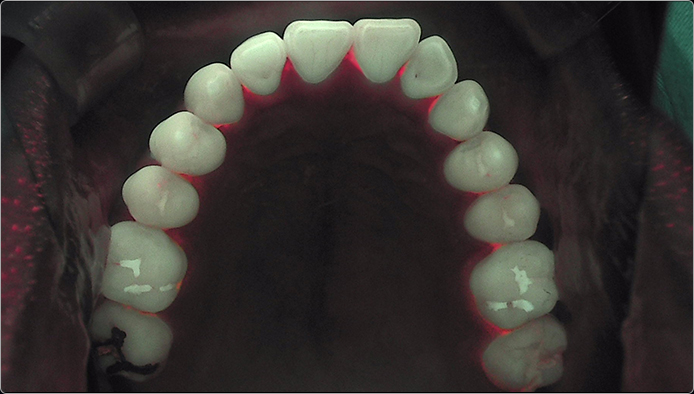

연세굿데이치과 | 40대 치아교정, 50대 치아교정, 중장년층 치아교정, 치주교정 연세굿데이치과의 중장년층 맞춤 치주교정은 단순한 치아 배열 교정이 아닌, 치아를 살리는 잇몸 교정입니다. 치조골 소실은 나이가 들수록 증가하며, 교정 상담 환자의 20~30%가 잇몸 질환을 동반합니다. 잇몸 상태가 불안정하면 교정 후 치근흡수, 치은퇴축 등 부작용이 발생할 수 있어, 치료 전 정확한 치주 검사와 처치가 필수입니다. 연세굿데이치과는 교정과·치주과 협진을 통해 심미 개선뿐 아니라 치아와 잇몸의 기능적 안정성까지 향상시켜 드립니다.